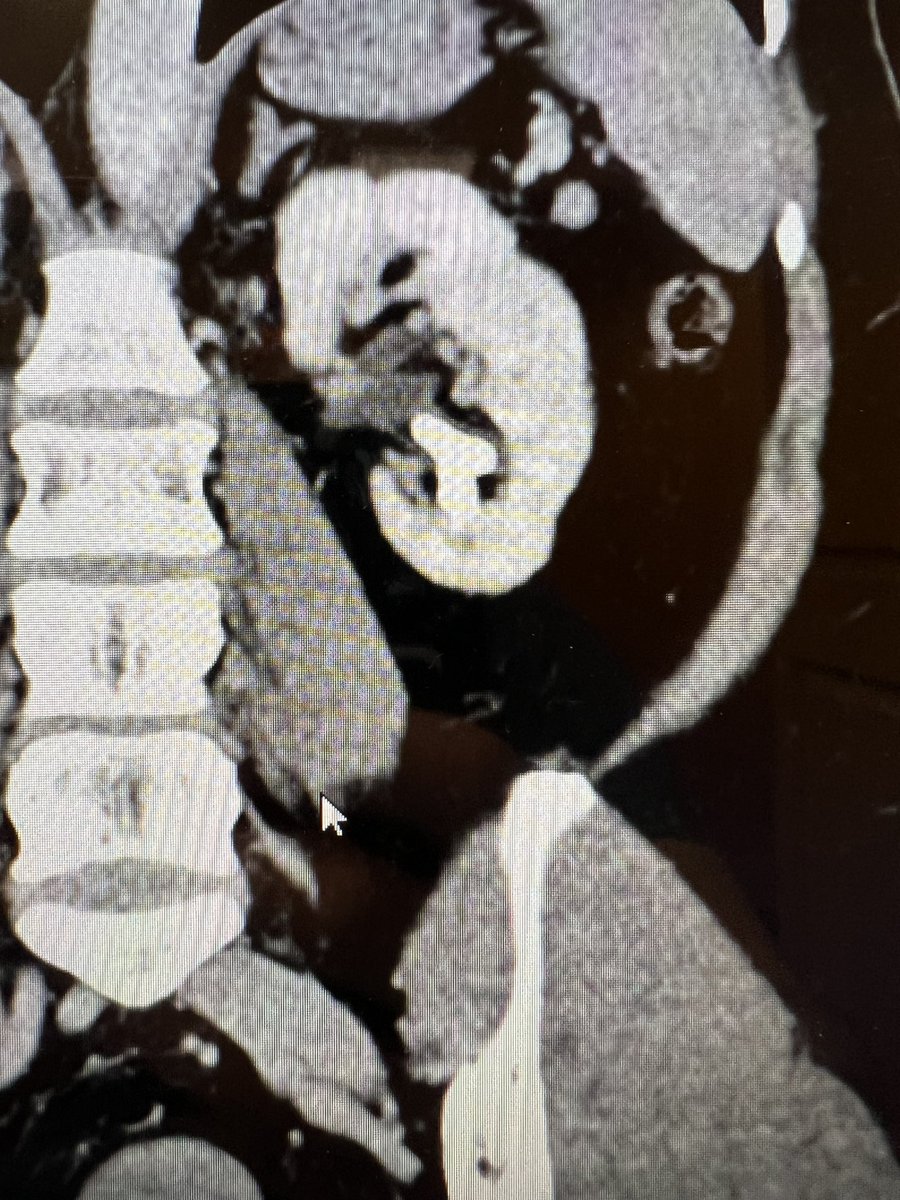

5 cases in and thoroughly impressed by the #CVACaspiration system. I’m generally hesitant to call anything a game-changer, but this partial staghorn didn’t stand a chance! #nostoneleftbehind @CalyxoInc

Great learning case: The fornix is very delicate and you can see splitting between calyx and papilla. 🔑Consider decompressing a hydronephrotic kidney upon entering the renal pelvis and use as little pressure as possible (even just gravity) #stonesmart @LHHUrology